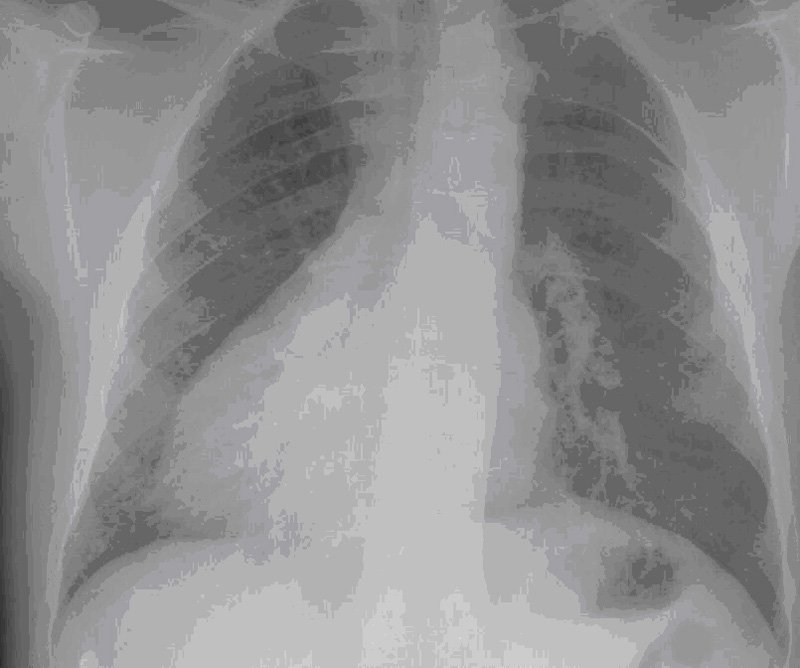

- Situs inversus total o parcial" (los órganos torácicos y/o abdominales situados en el lado opuesto al normal). Es una anomalía anatómica rara, que a menudo se asocia con múltiples malformaciones complejas. No existen datos concluyentes, pero parece que los trastornos que subyacen en la malposición de los órganos con respecto al eje izquierda - derecha en el embrión, están relacionados con las alteraciones ciliares.

- Bronquiectasias, dilataciones de los bronquios que suelen ser consecuencia de infecciones bronquiales de repetición, el acaloramiento mucociliar actúa como un mecanismo defensivo frente a las infecciones, cuando este sistema de defensa se altera se producen infecciones bronquiales de repetición y bronquiectasias.